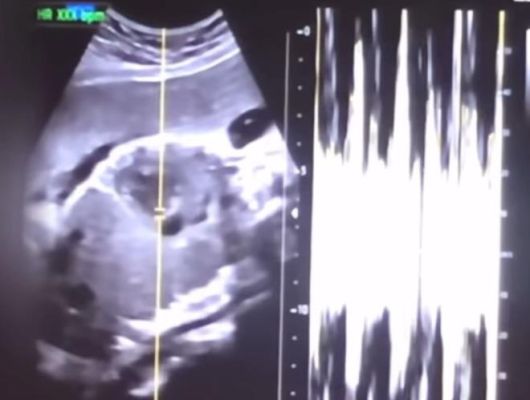

| 낙태한 산모의 초음파 사진과 심박 그래프 / 사진=연합뉴스, 서울중앙지검 제공 |